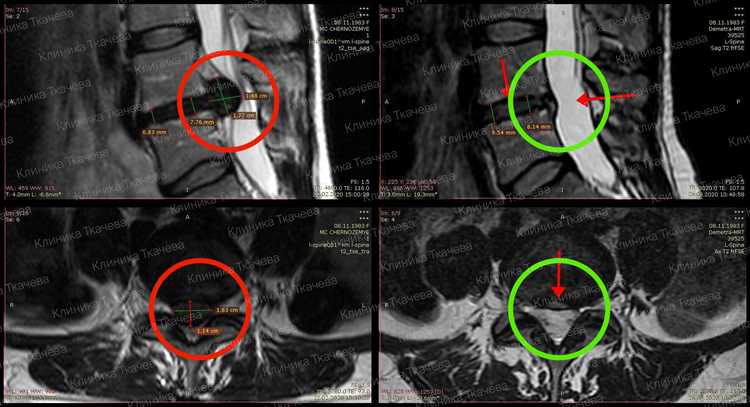

Для определения подходящего метода лечения грыжи необходимо обратиться к врачу-ортопеду или неврологу. Специалист проведет необходимую диагностику, включая осмотр и, возможно, визуализирующие исследования, такие как МРТ. На основе полученных данных врач сможет определить степень выраженности грыжи и рекомендовать подходящие методы лечения, включая возможность консервативных подходов. Индивидуальный подход к каждому пациенту является ключевым фактором для успешного результата.